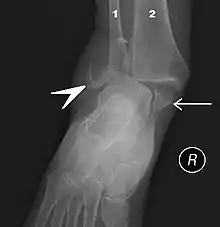

The initial evaluation of suspected ankle pathology is usually by projectional radiography ("X-ray").

For ligamentous injury, there are three main landmarks on X-rays: The first is the tibiofibular clear space, the horizontal distance from the lateral border of the posterior tibial malleolus to the medial border of the fibula, with greater than 5 mm being abnormal. The second is tibiofibular overlap, the horizontal distance between the medial border of the fibula and the lateral border of the anterior tibial prominence, with less than 10 mm being abnormal. The final measurement is the medial clear space, the distance between the lateral aspect of the medial malleolus and the medial border of the talus at the level of the talar dome, with a measurement greater than 4 mm being abnormal. Loss of any of these normal anatomic spaces can indirectly reflect ligamentous injury or occult fracture, and can be followed by MRI or CT.[25]